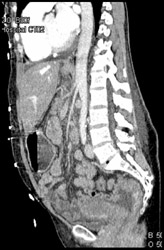

Vasculitis Kidney